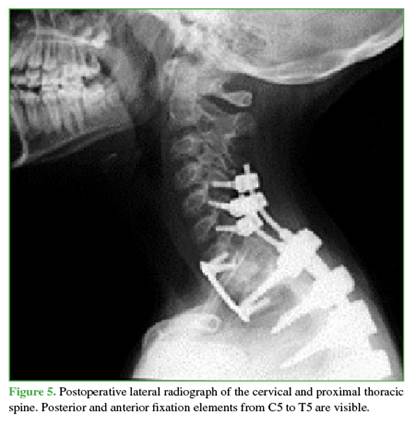

Forty-eight hours after embolization, the first surgical stage was performed. This involved posterior pedicle instrumentation from C5 to T5, decompression of C7, T1, and T2 (Figure 5), and tumor mass resection. Intraoperative bleeding was <500 mL.

Five days later, the second surgical stage was performed via an anterior approach, including T1 corpectomy with autologous bone graft placement.